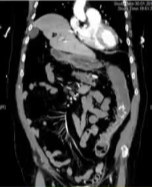

路径 A:CT 血管成像

CT angiography

· 对于血流动力学不稳定的患者,CT血管成像可快速定位活动性出血点(造影剂外溢征象)

· 优点:速度快、可同时评估全腹部

· 适用于:出血点未明确,或需要快速定位以便指导下一步介入